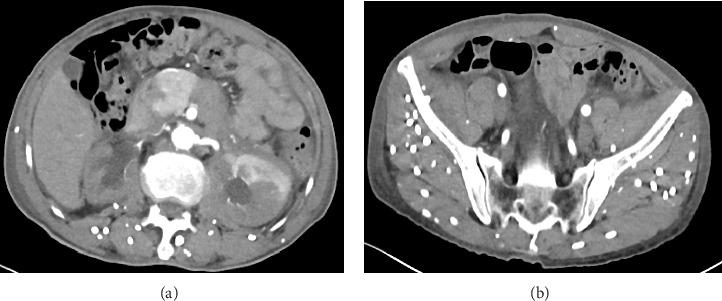

Encased by Infection: A Rare Case of Retroperitoneal Fibrosis Induced by Disseminated Cysticercosis.

Cysticercosis refers to a disease caused by the larvae of parasitizing various tissues and organs of the human body. It is reported that cysticercosis is most commonly caused by the central nervous system, and retroperitoneal fibrosis is rare. We report a case of retroperitoneal fibrosis caused by cysticercosis and a urinary tract obstruction caused by retroperitoneal fibrosis, which was successfully relieved by transurethral stenting. The complex pathophysiological mechanism of cysticercosis-induced retroperitoneal fibrosis requires further study. In the diagnosis and treatment of the disease, it is very important to consider the patient's epidemiological history and the presence of parasite infection.